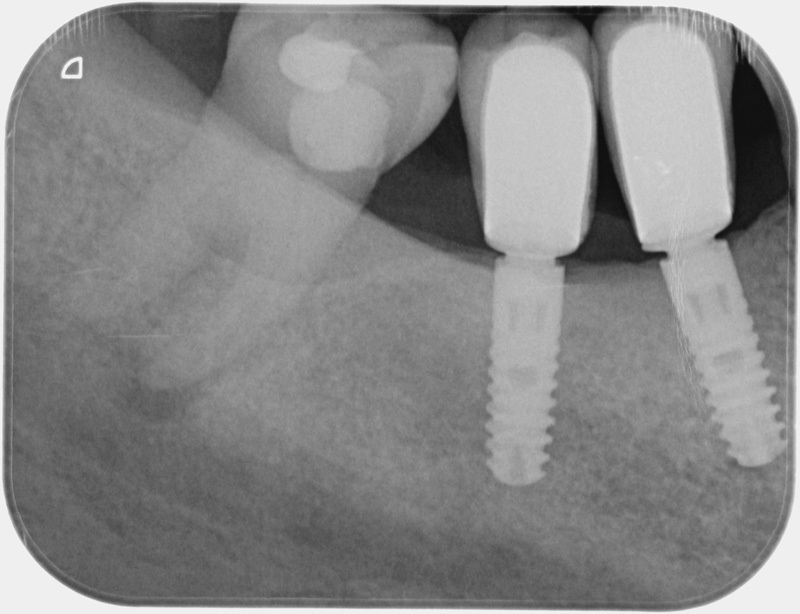

Après

• Traitement endodontique : Sous anesthésie locale et à travers la protection d’un champ opératoire nous accédons à la pulpe de la dent à soigner, puis aux canaux de ses racines que nous devons désinfecter. Ce soin nécessite l’élimination complète de la source de contamination (souvent la carie) parfois sous une ancienne reconstitution ou une couronne qu’il faut alors retirer. Une fois le nettoyage et la mise en forme des canaux réalisés, nous les obturons de façon hermétique avec un ciment et un matériau thermoplastique appelé Gutta Percha. Ceci afin d’empêcher une nouvelle prolifération bactérienne et d’assurer le maintien de la dent dans ses structures de soutien (ligament parodontal et os alvéolaire). L’ouverture effectuée au centre de la dent sera d’abord refermée avec un pansement provisoire avant d’envisager ensemble la reconstitution d’usage : un composite, un inlay-onlay ou une couronne.